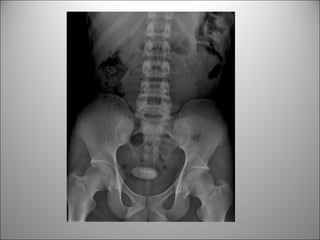

PATOLOGÍA RENAL - VESICAL

DETECCIÓN DE CÁLCULOS RADIO-OPACOS

 GLOBO VESICAL